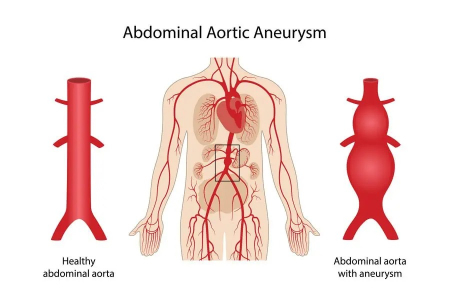

آنوریسم آئورت شکمی چیست؟

آنوریسم آئورت شکمی یک ناحیه بزرگ شده در قسمت پایین شریان اصلی بدن، به نام آئورت است. آئورت از قلب عبور کرده و از مرکز قفسه سینه و ناحیه شکم عبور می کند.

آئورت بزرگترین رگ خونی بدن است. پارگی آنوریسم آئورت شکمی می تواند باعث خونریزی تهدید کننده زندگی شود. درمان بستگی به اندازه آنوریسم و سرعت رشد آن دارد. درمان از چکاپ های سلامتی منظم و آزمایشات تصویربرداری تا جراحی اورژانسی متغیر است.